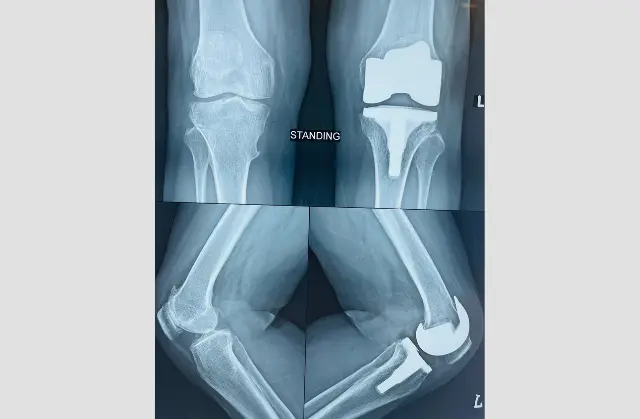

Meet Your Surgeon Dr. Shreyas Zalariya is a highly distinguished Orthopedic Consultant and Joint Replacement & Arthroscopy Surgeon. Having undergone rigorous Australian training, he combines international surgical standards with a compassionate, patient-first approach.

With advanced fellowship training from Australia, Dr. Shreyas Zalariya brings a global standard of orthopedic excellence to every patient. He specializes in cutting-edge, minimally invasive surgical techniques designed to minimize tissue damage and accelerate your return to an active life. Whether it is a complex joint replacement or a sports-related arthroscopy, Dr. Zalariya’s approach combines clinical precision with a deep commitment to long-term patient mobility and wellness.